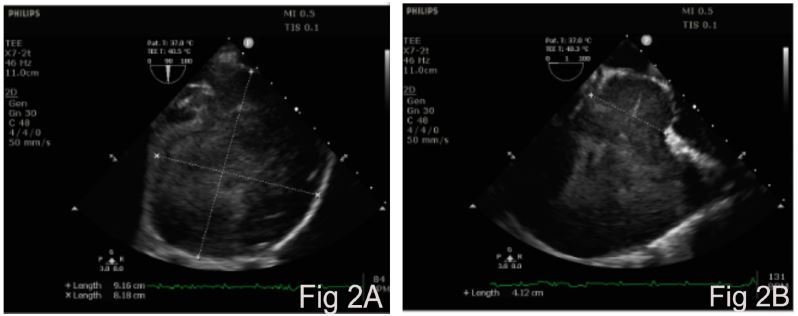

Intraoperative cardiac monitoring included transesophageal echocardiography (TEE), which showed a large RA diverticulum with a wide neck and spontaneous echo contrast (Figure 2A, 2B). In addition, it showed compression of the right ventricle (Supplementary video 1). The diverticulum was resected from within the RA and the communication was closed with a pericardial patch under hypothermic cardiopulmonary bypass (CPB). Histopathological examination of the diverticulum showed fibrous connective tissue and intima without a muscular layer. At three months’ follow-up, the patient was asymptomatic and TTE was normal.

Figure 2: Intraoperative transesophageal echocardiography image showing large right atrial diverticulum (Fig 2A) with wide neck (Fig 2B).